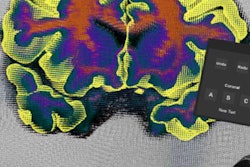

Above, 3D virtual model ultrasound view of fetus at 12 weeks. Below, 3D virtual model MRI view of fetus at 26 weeks. All images courtesy of the authors and RSNA.For the virtual reality viewing device, Werner and colleagues used the latest-generation Oculus Rift 2 (Oculus) headset. The device places users in an immersive sensory environment that includes even heartbeat sounds derived from fetal ultrasound scans. Users can simply move their heads to study 3D fetal anatomy close-up.

Above, close-up of fetus at 26 weeks. Below, visualization of internal structures at 27 weeks.The virtual reality model has several potential applications, such as assessment of fetal airway patency, according to the group. If doctors found an abnormal mass near the fetal airway, for example, they could use the 3D images and headset to assess the entire airway and make informed decisions about delivery.